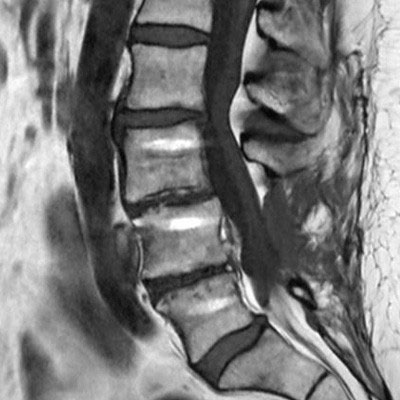

Lumbar Spine with metal implant, routine and fast

Utrecht Medical Center, The Netherlands

**Only for use with MR Safe or MR Conditional Implants by strictly following the Instructions for Use.